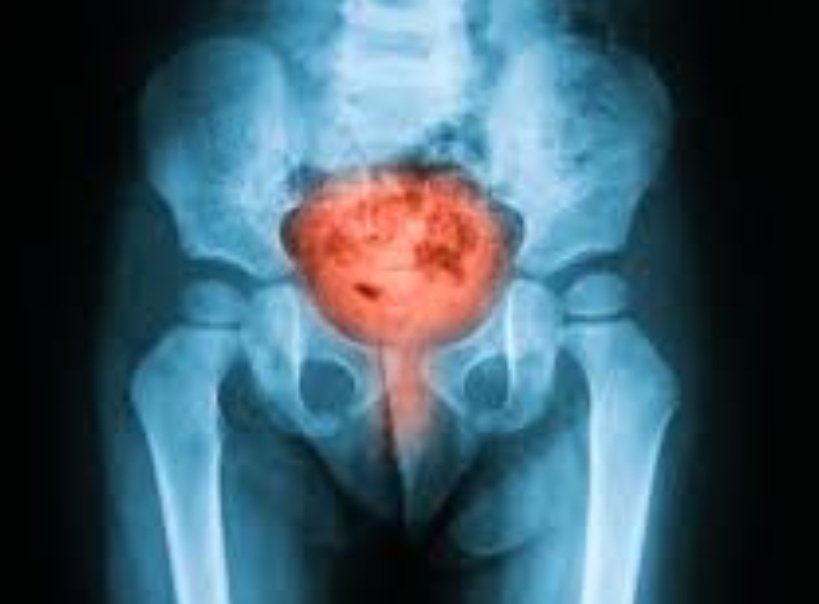

التهابات المسالك البولية تعتبر اكثر سبب لزيارة عيادة المسالك خاصه للنساء.

قد يحدث التهاب المسالك البولية في المثانه او الكلى او مجرى البول وعادة تختلف بالاعراض كما ذكرت سابقا .. واحيانا بالفحص او الاشعه ان استلزم الامر..